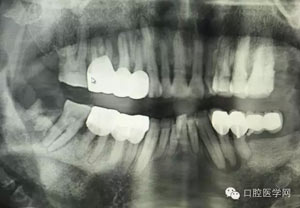

病例2:364647中齲的樹(shù)脂充填,現(xiàn)在樹(shù)脂的充填材料非常之多,有些時(shí)候,我們感覺(jué)有了好的材料我們就可以做出好的修復(fù),可是這是在我們有扎實(shí)的基本功的基礎(chǔ)上的,我們可以沒(méi)有那么好的樹(shù)脂,那么多的顏色選擇,修復(fù)的那么的逼真,但是我們至少要恢復(fù)患者牙齒的功能,將腐質(zhì)去除干凈,薄壁弱尖消除掉,選擇好適應(yīng)癥,給患者以盡可能好的修復(fù)。